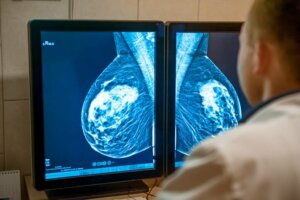

The classification of stages can be both clinical and pathologic. The clinical form is made based on the different imaging studies and biopsies performed. For its part, pathological determination is only possible after surgery, in which a specialist will analyze the extracted tissue.

During these stages, one of the preferred diagnostic methods are imaging tests such as mammography and a breast eco-sonogram. The prognosis is also usually good in most cases, depending on the presence of hormone receptors and the production of HER2 protein.